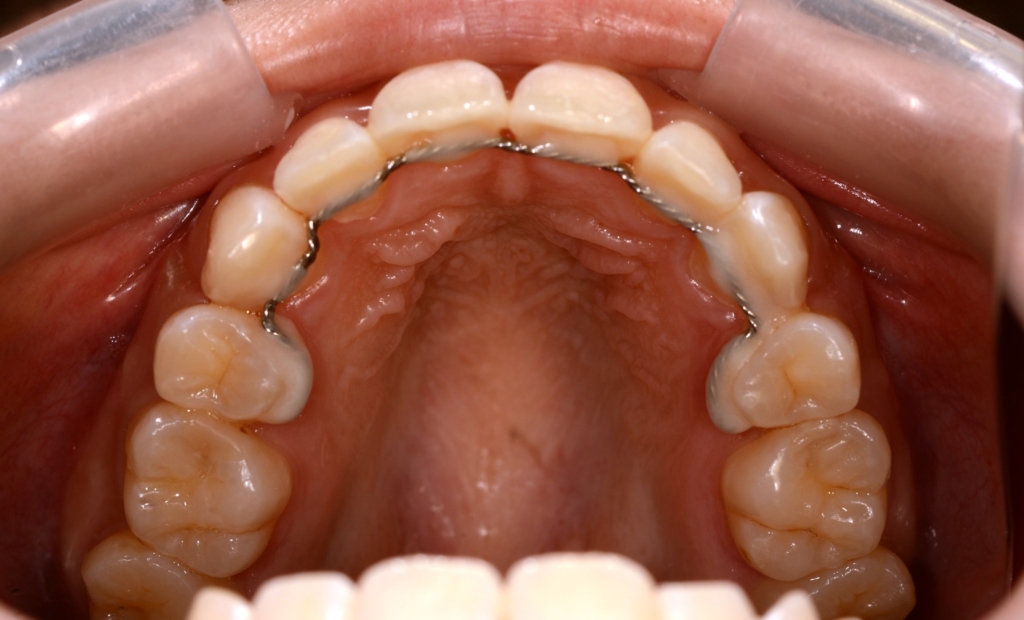

【保定】 上下ともフィックスタイプ&クリアリテーナー

あらためて、矯正治療前後の歯並びと口元の変化を比べてみましょう。

まずは、歯並びの変化です。